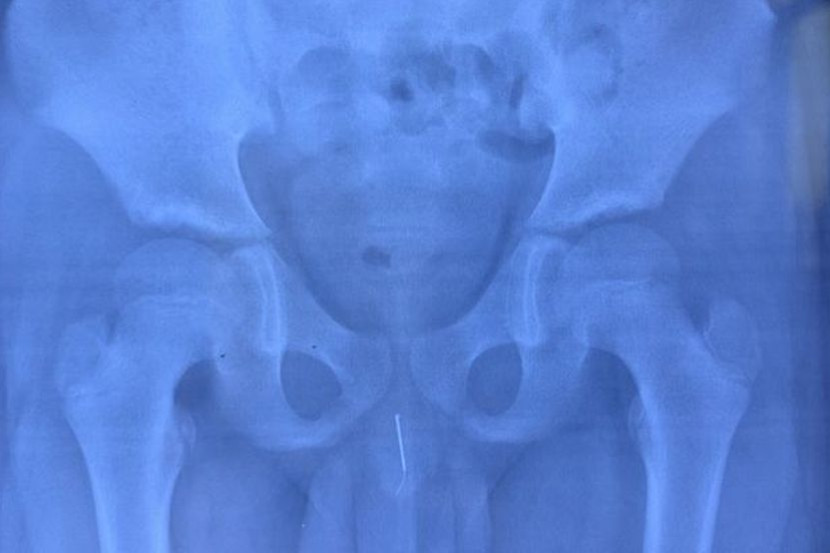

Hanya selepas menghantarnya untuk pemeriksaan X-ray, doktor dapat mengesan jarum itu dan dengan cepat membawa pesakit masuk untuk menjalani pembedahan.

Doktor melakukan endoskopi dan menggunakan sepasang forsep yang halus untuk mengeluarkan jarum dalam pembedahan invasif minimum, sebelum Huang dibenarkan pulang ke rumah. - Daily Star